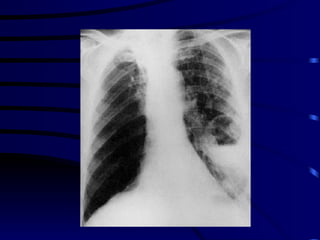

Definition Syndrome caused by acute infection caused by a wide variety of microorganisms, characterized  by clinical and/or radiological signs of consolidation of a part or parts of one or both lungs .

Clinical Definition Symptoms of acute LRT infection  a) Cough, sputum,chest pain b) Fever,sweating,shiver, aches and pains New focal chest signs on examination  OR New  radiographic pulmonary infiltrates

SEVERE CAP There is no universally accepted definition of severe CAP: 1. Respiratory frequency >30 breaths min at admission 2. Severe respiratory failure defined by a Pao2/Flo2 ratio <250  3. Requirement for mechanical ventilation 4. Chest radiograph showing    a) bilateral involvement    b) involvement of multiple lobes   c) an    in the size of the opacity by   50 % within 48 h of  admission  5. Shock ( SBP < 90 mmHg or DBP < 60 mmHg)  6. Requirement for vasopressors for more than 4 h 7. Urine output < 20 ml/h or acute renal failure requiring dialysis

SOME FACTS ABOUT CAP The  etiologic agent  causing CAP cannot be accurately predicted from clinical or radiological features The term ‘ atypical pneumonia ’ should be abandoned Elderly patients  with CAP more frequently present with non specific symptoms and are less likely to have fever Radiological resolution  lags behind clinical improvement  Radiological resolution  is slow in the elderly and cases of multilobar involvement.